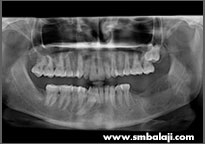

CASE II

X-ray showing 6 impacted teeth- upper right and left third molars and lower right and left third and second molars

All impacted teeth removed